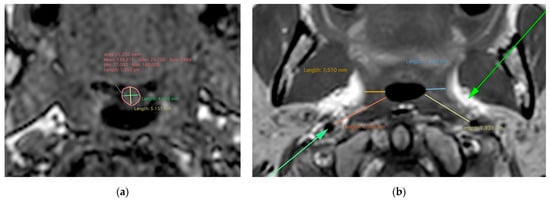

| Mandibular–hyoid distance | A: 0 | C: 0.569 (0.312, 0.746) | E: 0.431 (0.254, 0.688) |

| Hyoid–cervical tangent distance | A: 0 | C: 0.685 (0.510, 0.805) | E: 0.315 (0.195, 0.490) |

| Hyoid–cervical tangent distance | 0.550 (0.236, 0.760) | 0.811 (0.595, 0.918) |

| Soft palate length | 0.724 (0.504 0.854) | 0.429 (0.017, 0.715) |